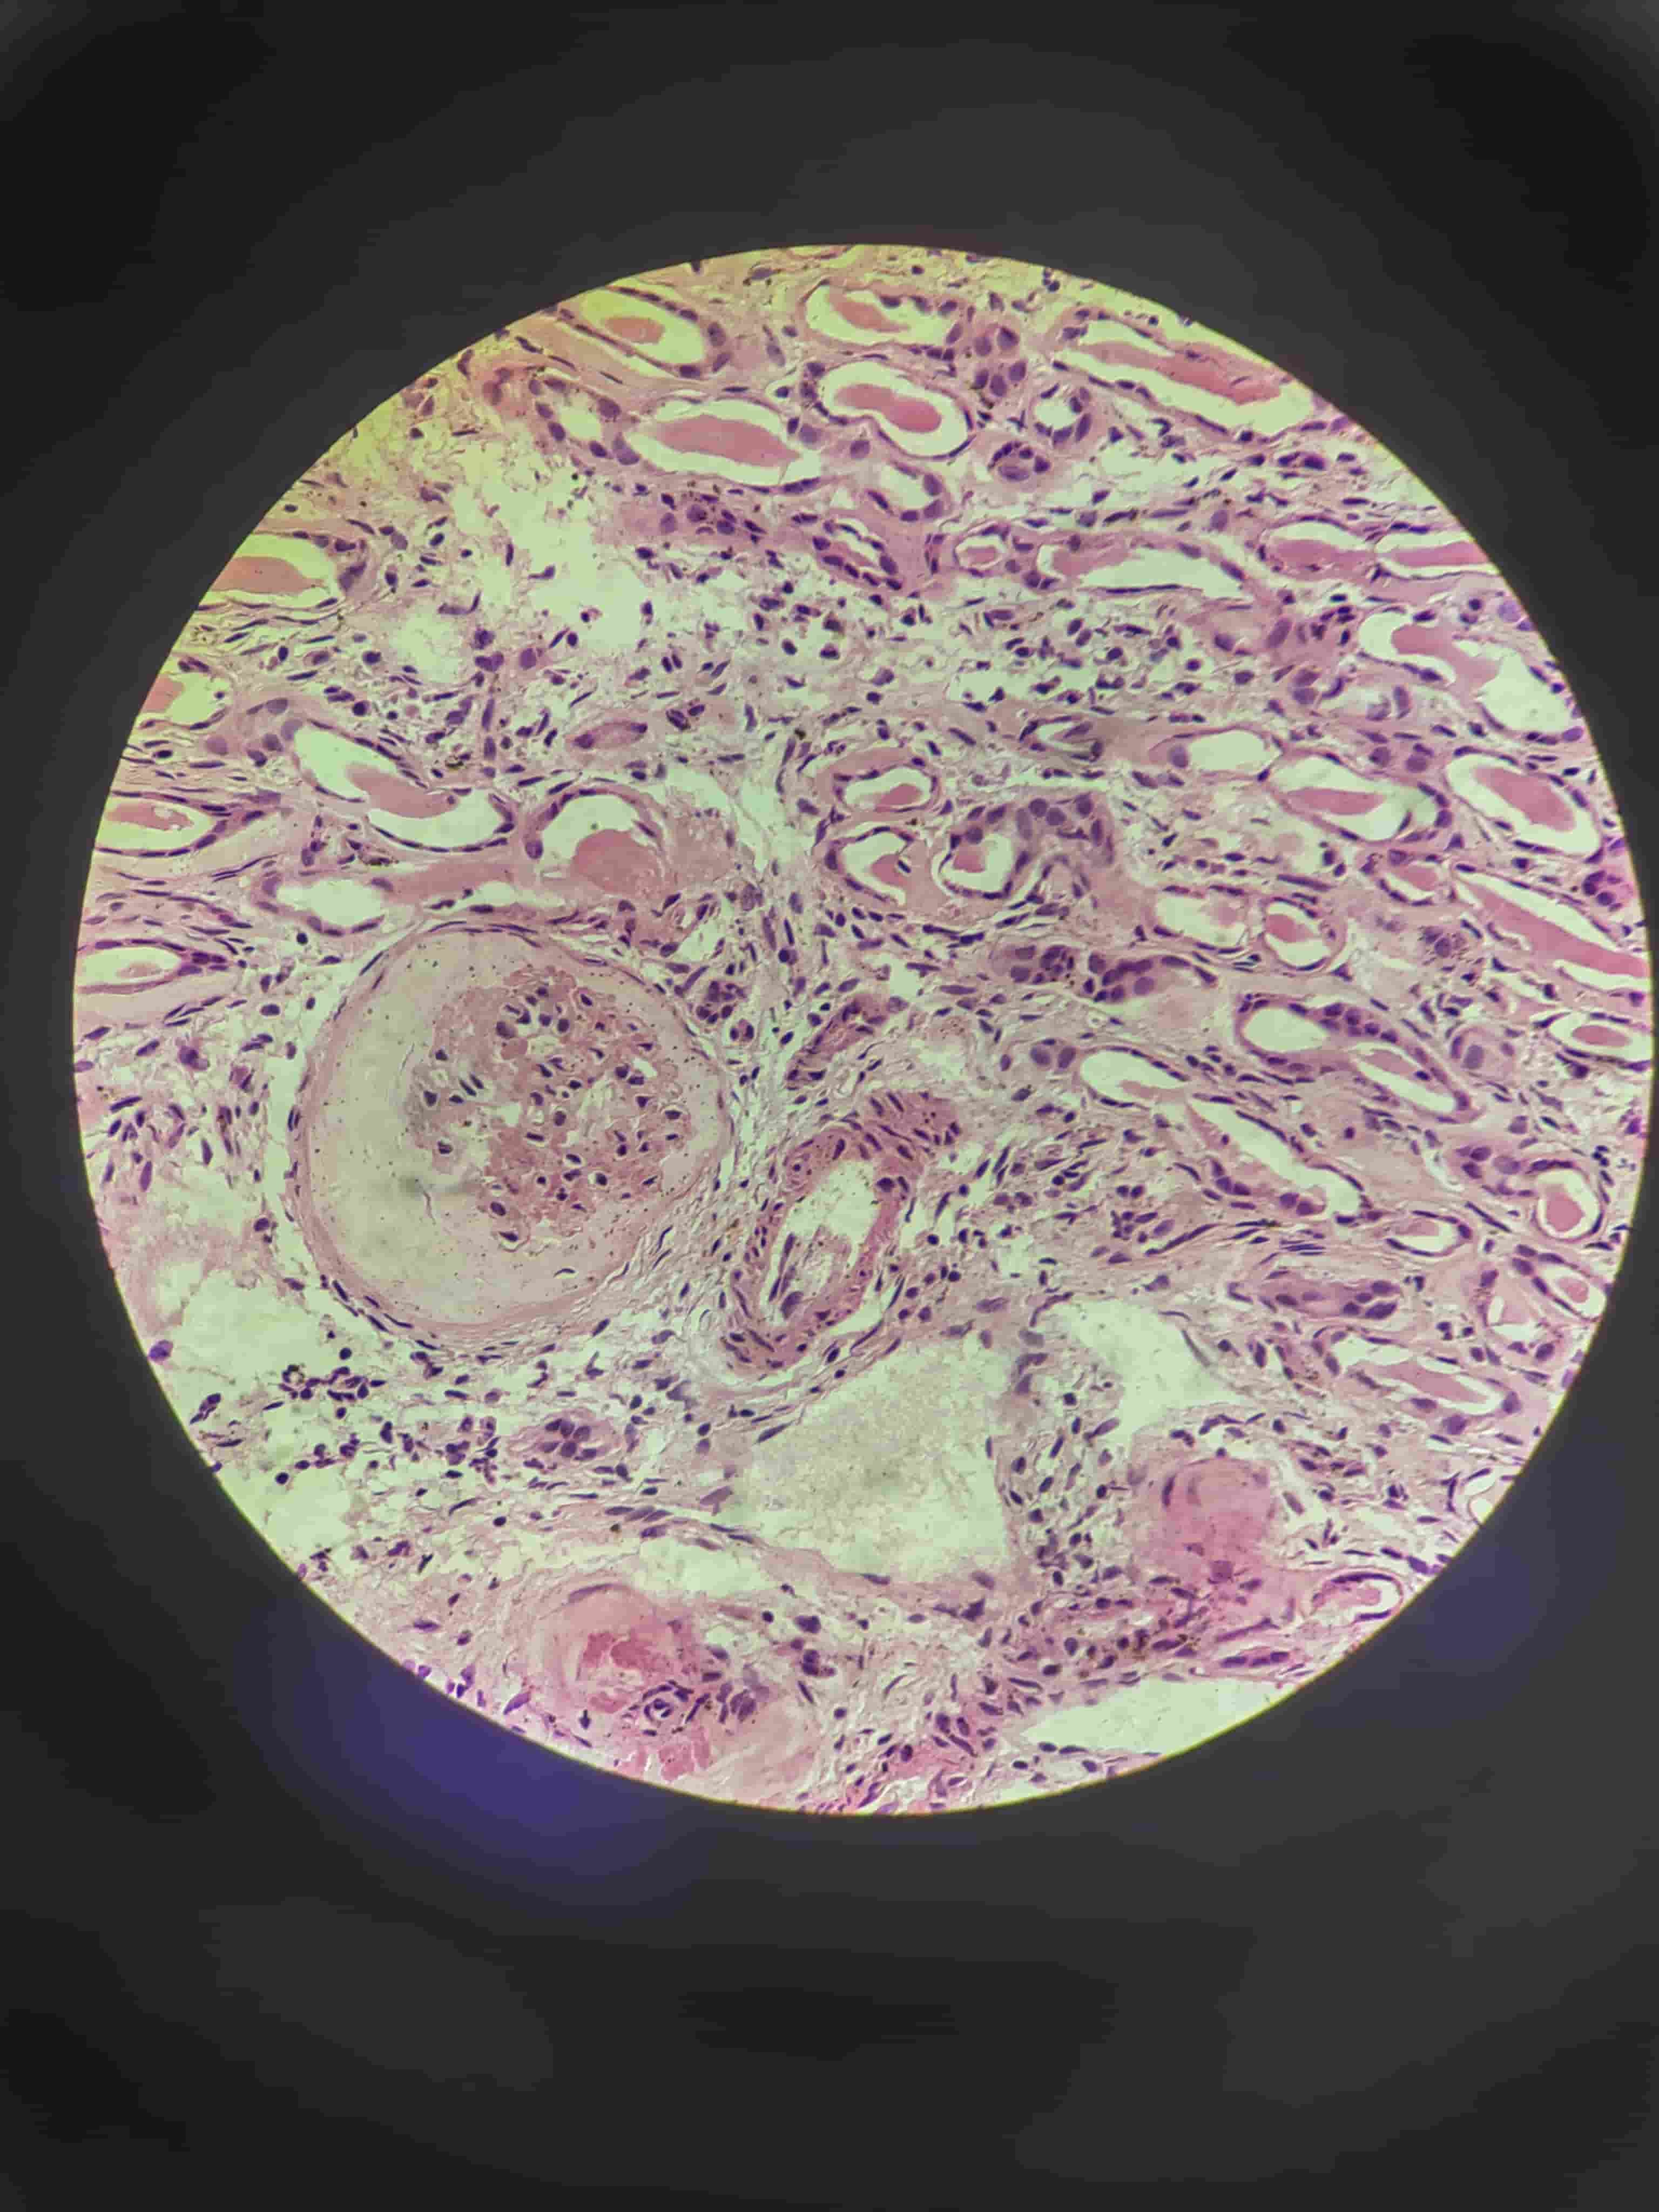

硅肺.0.0

硅肺.0.1

硅肺.0

硅肺.1

硅肺.2

硅肺